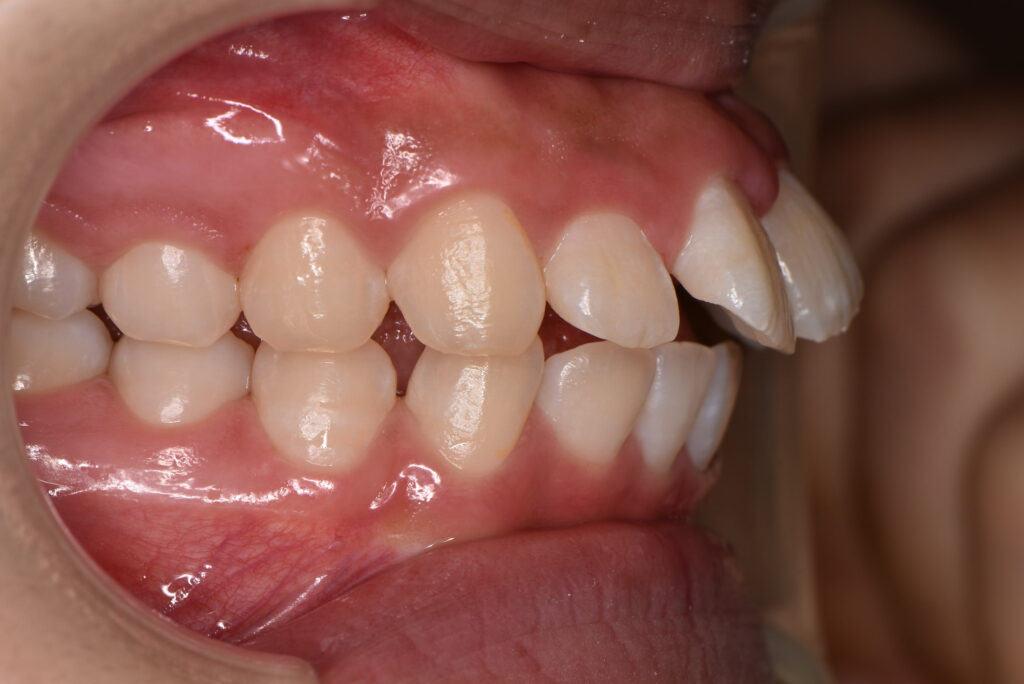

【ワイヤー矯正】

矯正前(正面・側貌)

矯正後(正面・側貌)

主訴出っ歯、すきっ歯

初診年齢15歳

治療内容、装置頬側ブラケットを用いた永久歯全体の矯正治療、アンカースクリュー

抜歯の有無抜歯有

(左右下顎第二小臼歯、左右上顎第一小臼歯抜歯)

治療期間20ヶ月

費用総額1,097,800円(税込)

(相談料、検査料、診断料、動的治療費、抜歯費、アンカースクリュー埋入、除去費、保定期間料等含む)

治療のリスク、副作用歯の移動に伴う痛み

上下顎前歯部の歯根吸収

装置による口内炎

ブラッシング不良によるむし歯、歯周炎